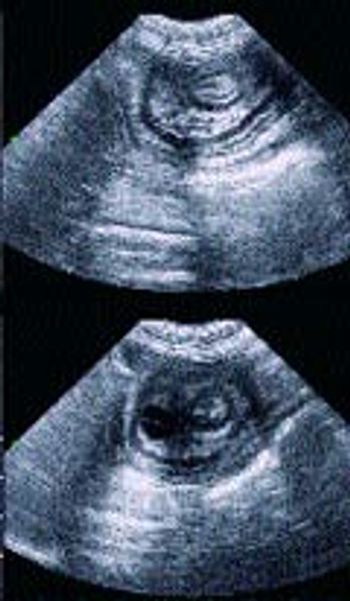

Signalment: Feline, Domestic Shorthair, 10 years old, female spayed, 12 lbs.

Q. Please provide a brief review of diagnosis and treatment of feline asthma.